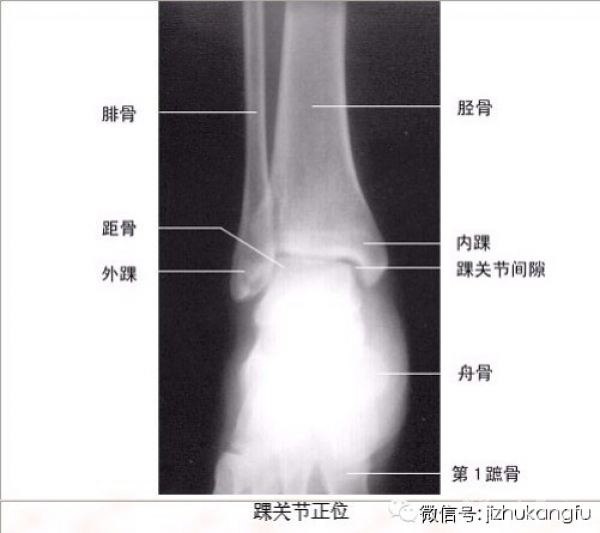

1四肢关节